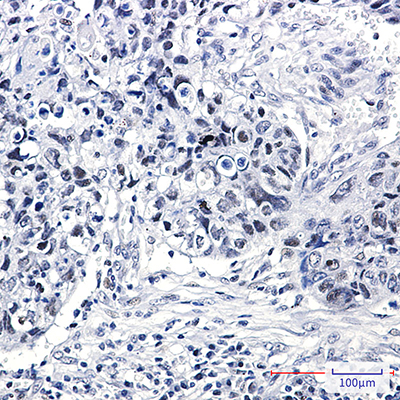

WB,IHC-P

WB: 1:500-1:1000 IHC: 1:50-1:100

Facilitate pre-mRNA processing and transport of mRNA from the nucleus to cytoplasm. hnRNP K contains three unique structural motifs termed KH domains that bind poly(C) DNA and RNA sequences. Intricate architecture enables hnRNP K to facilitate mRNA biosynthesis, transcriptional regulation, and signal transduction. Research studies have shown that cytoplasmic hnRNP K expression is increased in oral squamous cell carcinoma and pancreatic cancer, and may be a potential prognostic factor.